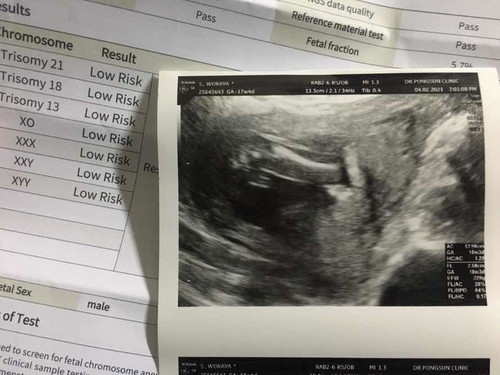

ผลตรวจดาวน์ออกแล้วแม่โล่งมากค่ะ

เมื่อคืนแม่ไปรับผลตรวจมา ความเสี่ยงน้อย คุณหมอซาวให้ดูอย่างละเอียดแขนขานิ้วมือ นิ้วเท้า ปาก แม่สบายใจขึ้นเยอะ หลังจากทะเลากับพ่อน้องขอไปตรวจเลือดที่คลีนิก(เงินตัวเอง😅) เพื่อความสะบายใจของแม่ เพราะแม่คิดว่าถ้าลูกเป็นแม่ยอมรับเลยค่ะว่าไม่สามรถดูแลน้องได้ เป็นกำลังใจให้แม่ๆ ทุกคนนะคะ #17w